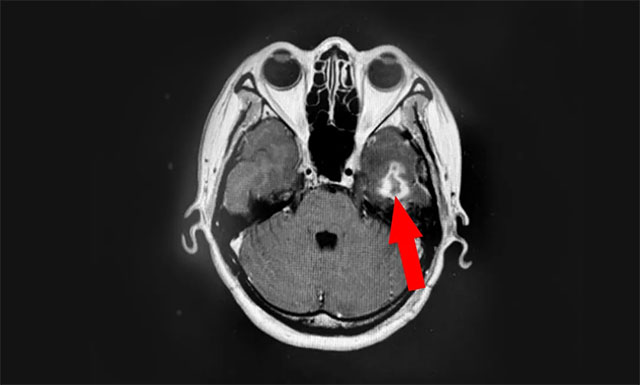

近期,患者為尋求進(jìn)一步治療,來到上海藍(lán)十字腦科醫(yī)院。醫(yī)院腫瘤科(放療)頭部伽瑪?shù)督M主任陳琦及醫(yī)生團(tuán)隊結(jié)合患者病情變化,為湯女士行立體定向穿刺引流聯(lián)合伽瑪?shù)吨委。?jīng)一段時間住院恢復(fù)后復(fù)查,病灶占位較前進(jìn)一步縮小,腫瘤進(jìn)展得到了較好地控制,目前已順利出院。

▲ 伽瑪?shù)吨委熀髲?fù)查,可見病灶占位明顯縮小